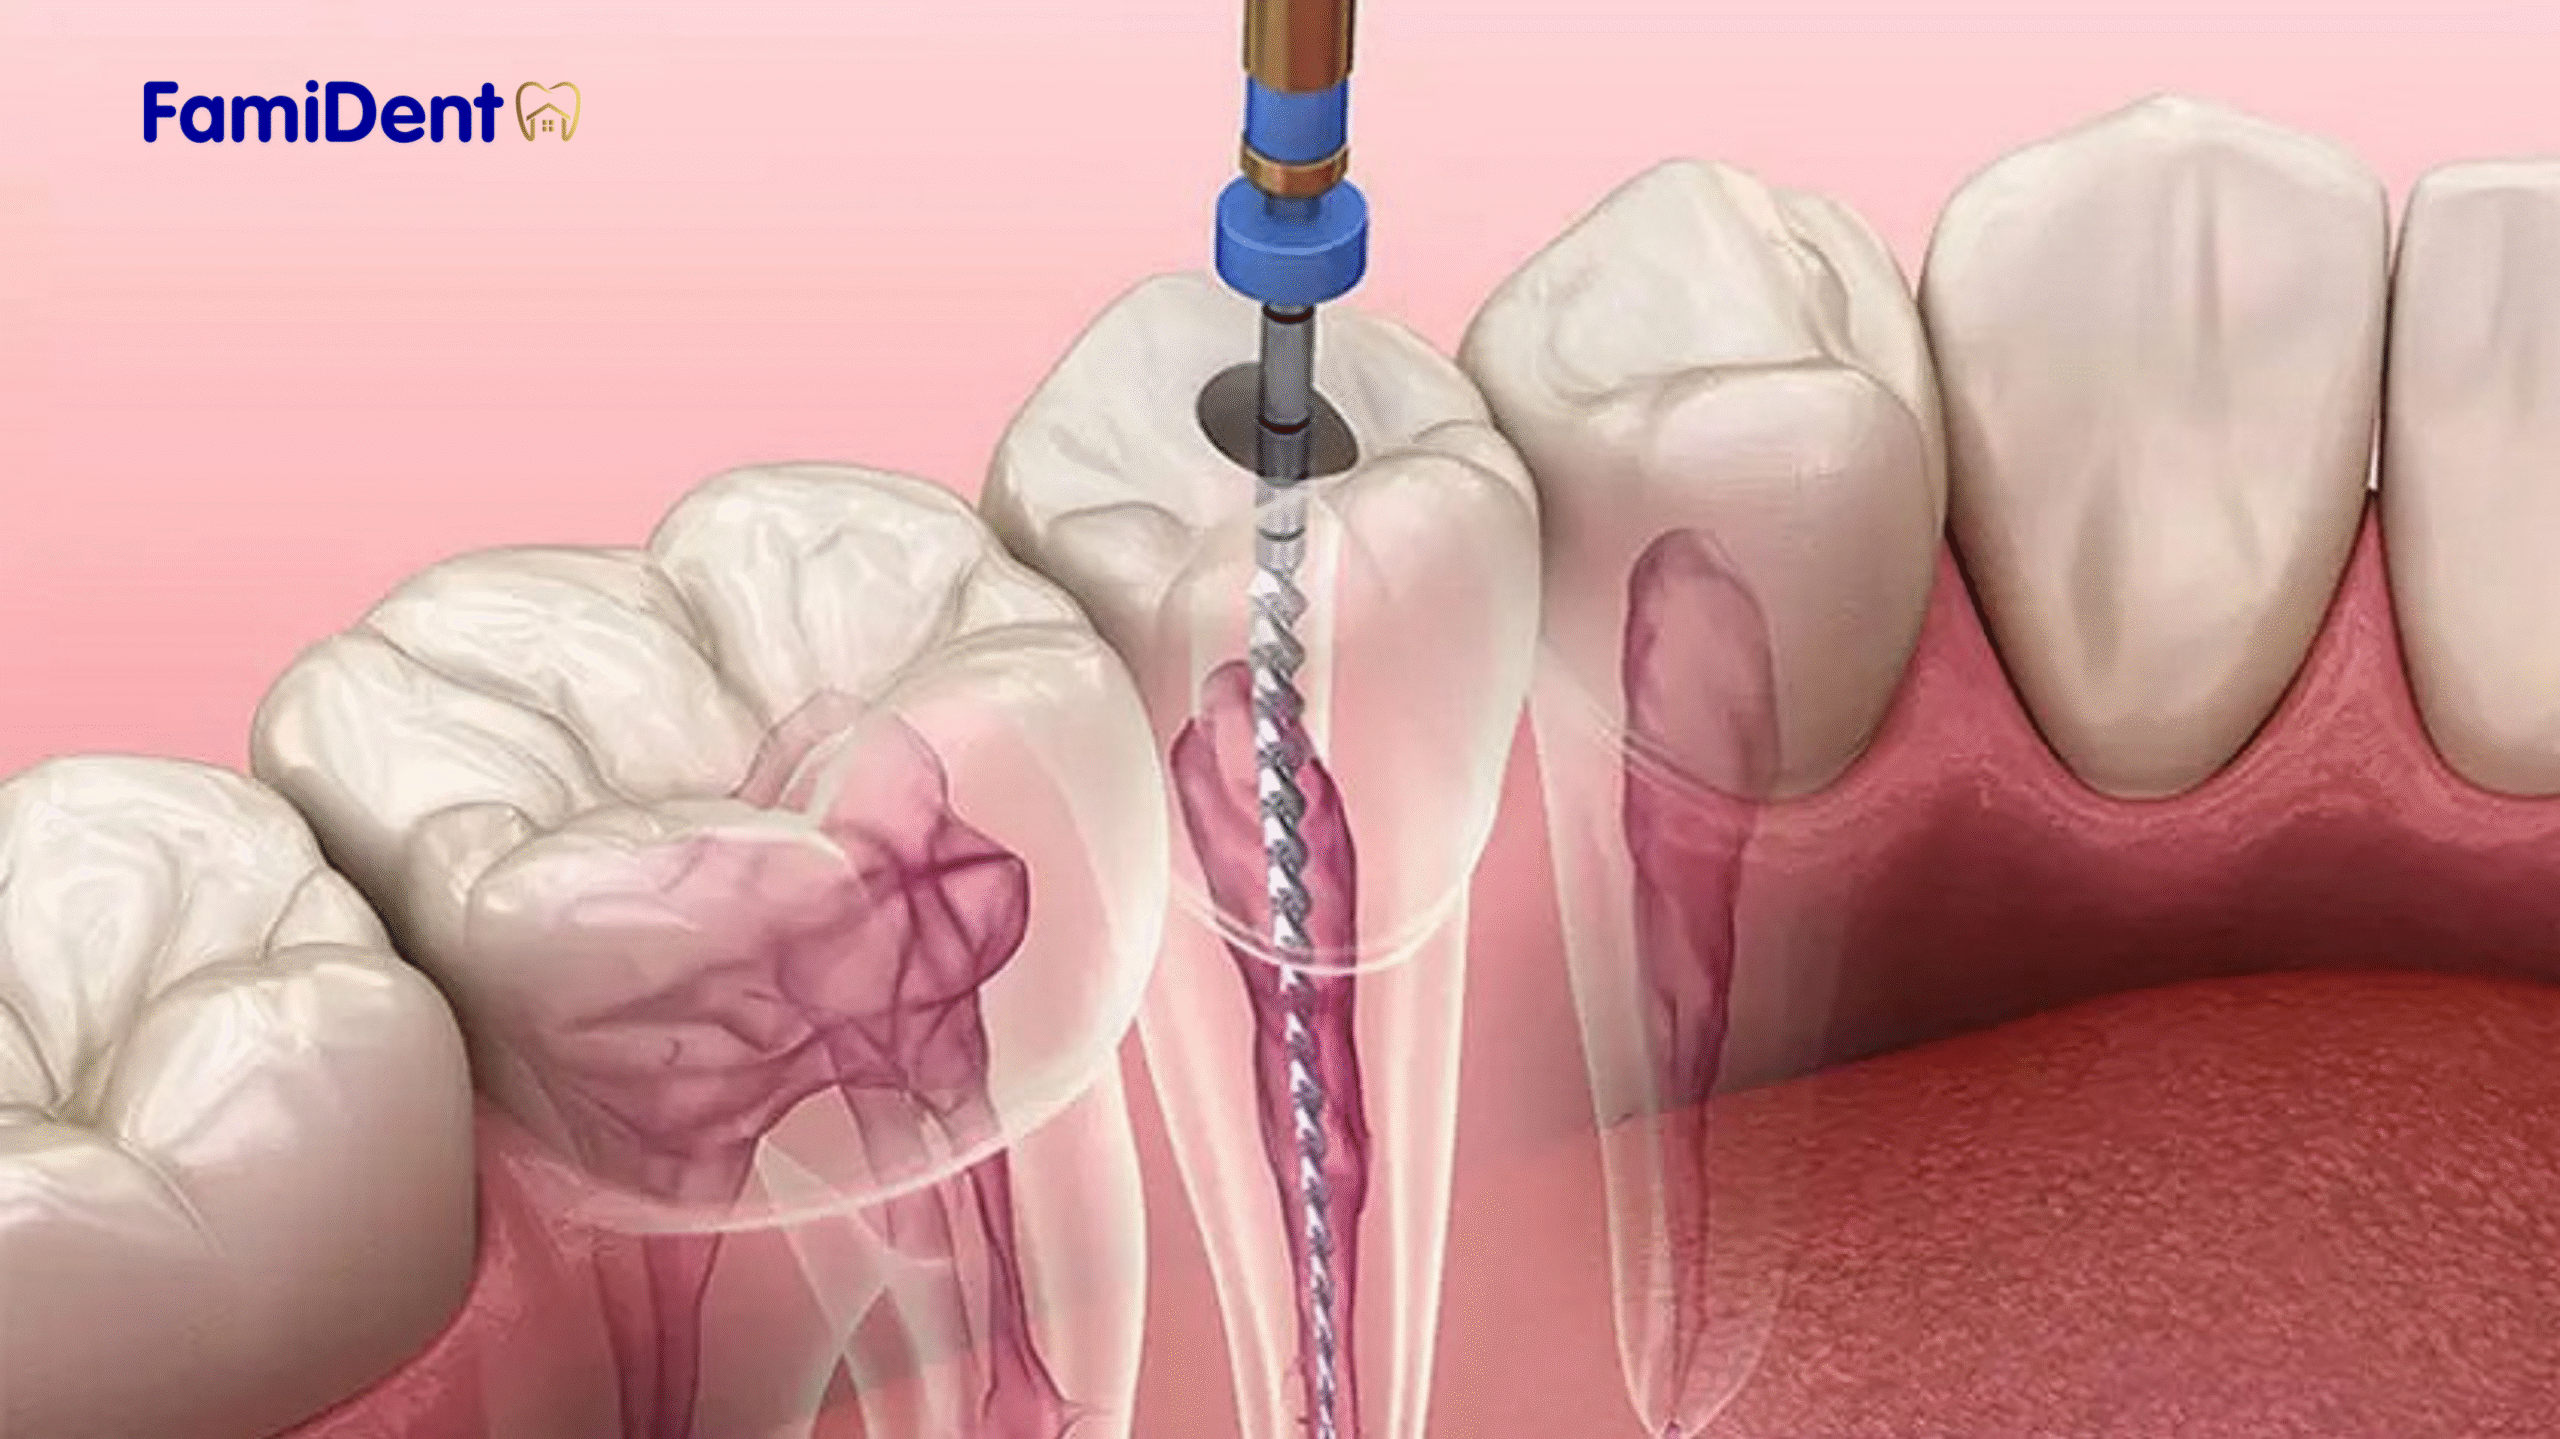

Lấy tủy răng là quá trình loại bỏ phần tủy răng bị viêm hoặc nhiễm trùng (phần mô mềm bên trong răng chứa dây thần kinh và mạch máu). Sau khi lấy tủy, răng sẽ được làm sạch, khử trùng và trám bít để ngăn ngừa vi khuẩn xâm nhập. Mục tiêu của phương pháp này là bảo tồn răng, tránh nguy cơ phải nhổ răng.

- Loại bỏ tủy răng: Bác sĩ sử dụng dụng cụ chuyên dụng để mở khoang tủy, loại bỏ mô tủy bị viêm hoặc nhiễm trùng.

- Làm sạch và khử trùng: Khoang tủy được làm sạch kỹ lưỡng và khử trùng để loại bỏ hoàn toàn vi khuẩn.

- Trám bít ống tủy: Ống tủy được lấp đầy bằng vật liệu chuyên dụng để ngăn ngừa vi khuẩn xâm nhập trở lại.